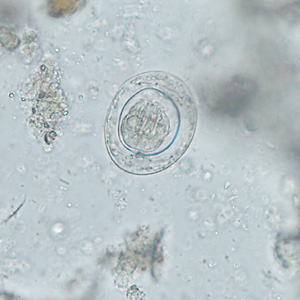

A 42-year-old man with a history of living abroad in Peru for a year returned home to the United States. He reported to his health care provider that he had been experiencing vague intermittent abdominal discomfort. A stool specimen was collected and processed for ova-and-parasite (O&P) examination. Figures A–E show what was observed at 400x magnification in moderate numbers; Figures A and B are of the same object in different focal planes. The object in Figure D is approximately 33 micrometers in diameter. What is your diagnosis? Based on what criteria?

Figure D